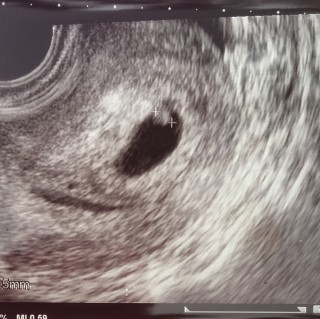

待望の3人目を妊娠して6週3日で胎芽は2mmくらいでしたが2mmでもチカチカとしっかり心拍確認できました!何回妊娠しても心拍確認はほんとドキドキします